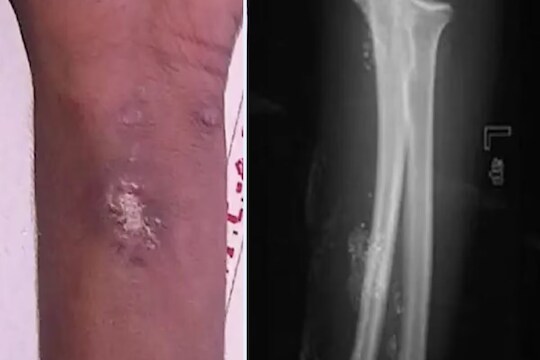

15 वर्षाचा मुलगा 2 वर्षापासून स्वतःला इंजेक्शन देत होता. तो स्पायडर मॅन बनू शकेल या आशेने तो स्पायडरलाही स्वतःला चावून देत होता. नॅशनल सेंटर फॉर बायोटेक्नॉलॉजी इन्फॉर्मेशनच्या अहवालात त्याने जाणूनबुजून शरीरात इंजेक्शन टोचल्याचं सांगितलं. मुलगा भारतातील ट्रॉमा सेंटरमध्ये गेला होता, जिथे डॉक्टरांना मुलाच्या डाव्या मनगटावर अनेक न बरे होणारे अल्सर आढळले. त्याने मर्क्युरी इंजेक्शन घेतले होते. हेही वाचा - shocking step : बायकोने दारु पिण्यापासून थांबवले, रागाच्या भरात नवऱ्याचं धक्कादायक पाऊल इंजेक्शन घेण्यामागे काही मानसिक समस्या असल्याचा संशय डॉक्टरांना होता. त्यावर मुलाने आपण जाणूनबुजून पारा टोचून घेतल्याचा खुलासा केला. अहवालात असे म्हटले आहे की हा मुलगा एक्स-मेनच्या मर्करी या पात्रापासून प्रेरित होता. डॉक्टरांनी सांगितले की त्याला कोणतीही मानसिक समस्या नाही आणि तिचा IQ सामान्य आहे. मुलावर शस्त्रक्रिया करण्यात आली आणि शस्त्रक्रियेनंतर तो बरा झाला. मुलांवर देखरेख ठेवली पाहिजे आणि मुलांनी घरी असे करण्याचा प्रयत्न करू नये याची काळजी पालकांनी घेतली पाहिजे. दरम्यान, आजकाल चित्रपट पाहून लहान मुलं तसंच करायला बघतात. कधी कधी ते स्वतःसोबतच खूप धक्कादायक करुन घेतात. ज्यातं त्यांनाही भान नसतं.